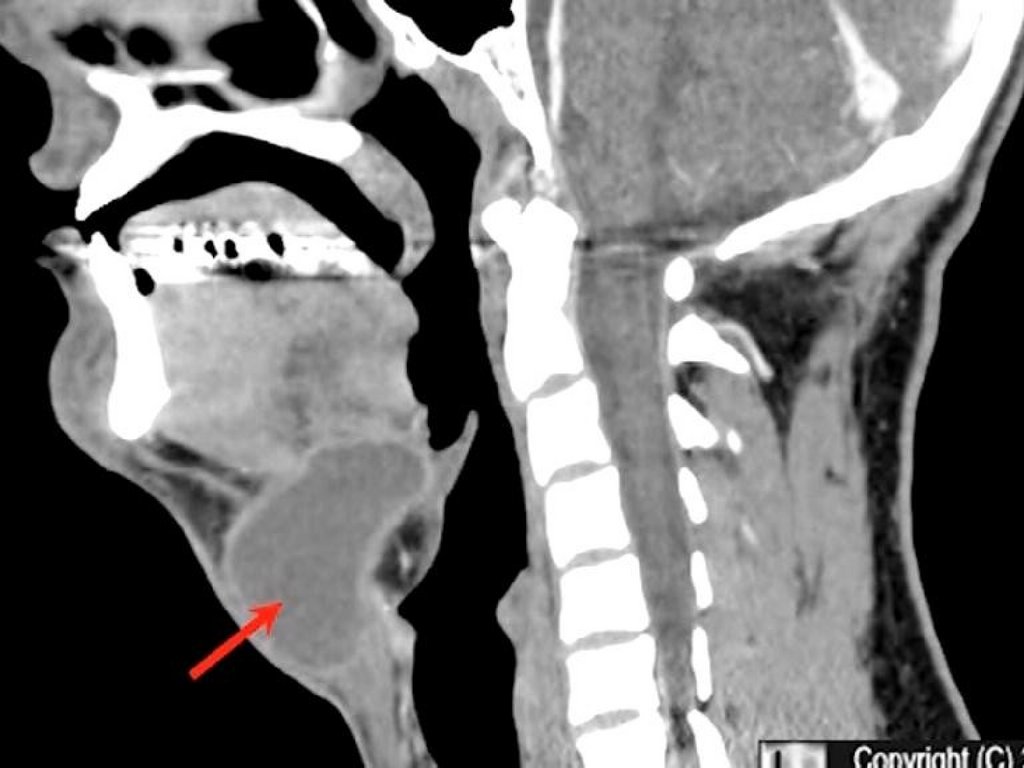

Щитовидная железа

ЩЖ имеет форму бабочки и

располагается на шее спереди от

трахеи и снизу от гортани. Она состоит

из двух долей, соединенных

перешейком.

Несмотря на небольшой размер ЩЖ,

гормоны, вырабатываемые в ней,

участвуют практически во всех

процессах организма. Основной

функцией ее является поддержание

нормального метаболизма (обмена

веществ) в клетках организма.

Глот ка

Т рахея

Щит овидная

железа